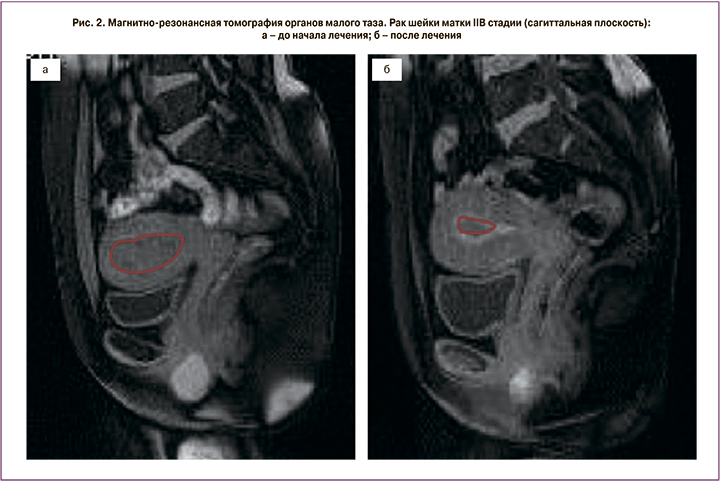

Пациентка Д., 43 лет, обратилась с жалобами на боли внизу живота, кровянистые выделения из половых путей различной интенсивности. При обследовании установлен диагноз РШМ IIB стадии. Биопсия подтвердила плоскоклеточный гистотип опухоли. По данным МРТ малого таза опухоль максимальным размером 67 мм распространялась на тело матки и инвазировала клетчатку параметрия справа. Была выполнена двусторонняя ХЭ маточных сосудов лекарственно-насыщаемыми микросферами Hepaspheres. В качестве цитостатика использовали препарат оксалиплатин в дозировке 100 мг.

Через 3 недели после операции выполнена МРТ малого таза с контрастированием. Эффект от лечения расценен как частичный ответ (рис. 1, 2), что позволило провести хирургическое лечение в объеме операции Вертгейма, после чего пациентка получила адъювантный курс лучевой терапии. По настоящее время рецидива не зарегистрировано, время наблюдения составило 26 месяцев.